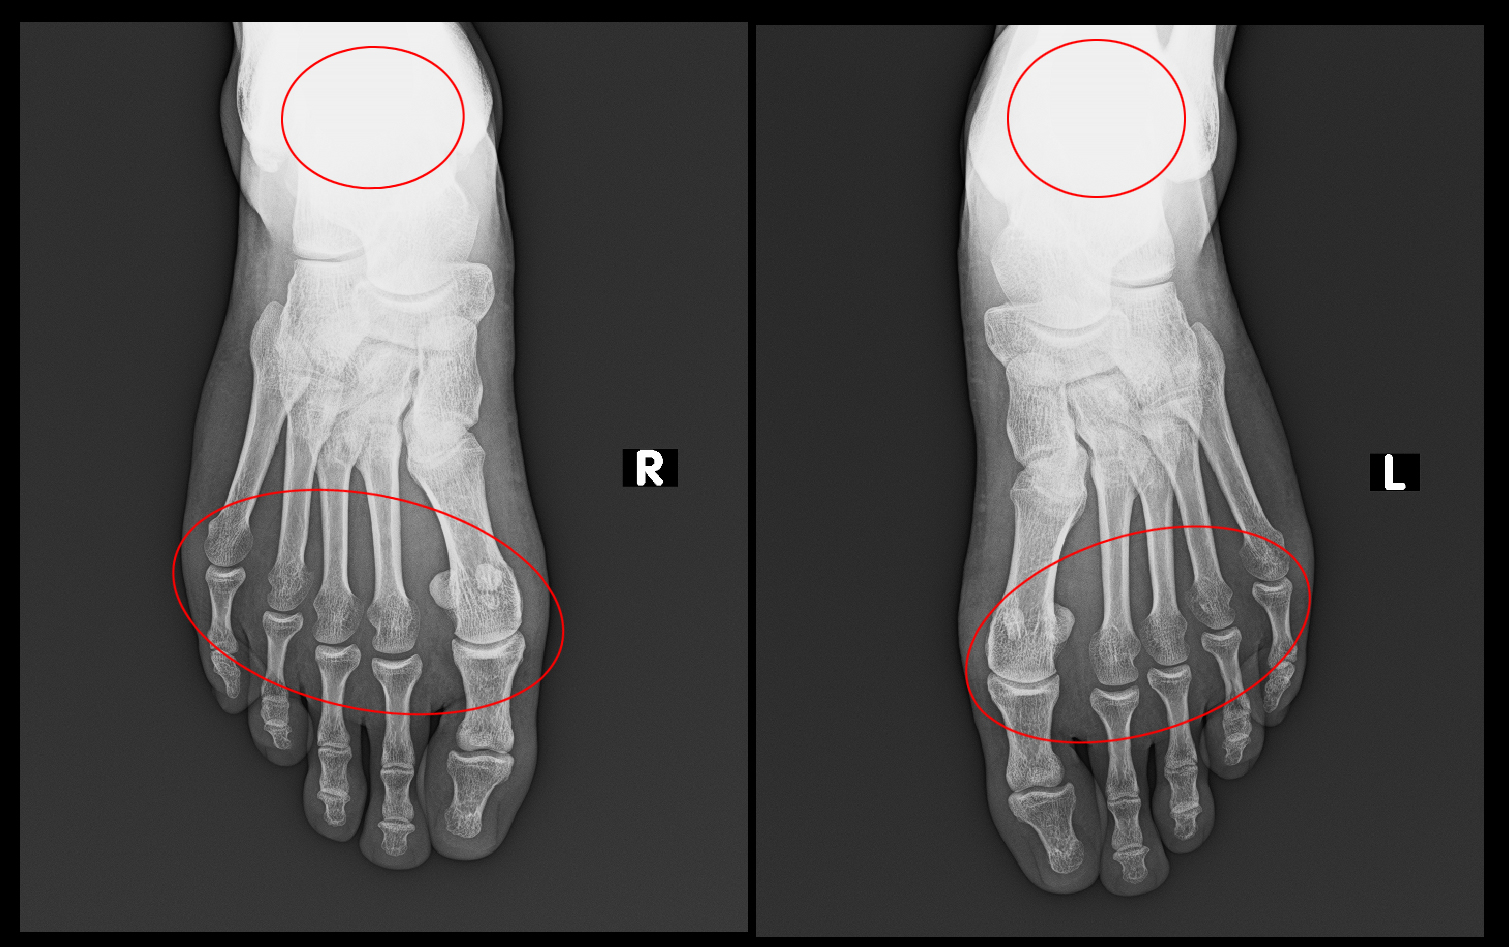

休薬後8か月の令和5年4月8日両側踵骨部痛、両前足部足底痛、左手関節痛で再診されました。

366才男Xp1.jpg

4月15日に両側足部のMRI検査を施行しています。

両側踵骨部痛の原因は両側踵骨(かかとの骨)全体に軽度の高輝度所見を認め、リウマチによる骨変化と診断しました。

366才男MR1b.jpg

両側前足部の痛みは、右第2趾・第4趾のMP関節炎(赤矢印)と左第2趾・第3趾・第4趾のMP関節炎(赤矢印)と診断され、両側第4中足骨の骨頭部には高輝度所見(オレンジ矢印)を認め、これもリウマチによる骨変化と診断しました。

366才男MRI1b.jpg